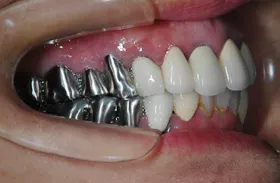

インプラントでの臼歯のかみ合わせの不調和改善例

■治療前

全ての歯の高さが、波を打ったような状態になって、咬み合わせが難しくなっています。

■治療後

術前にあった、歯の高さの不調和の問題が改善できています。

| 主訴 | かみ合わせが悪くかみにくい・時々顎関節症による痛みがある |

|---|---|

| 治療方法 | 補綴治療(波打ったような歯の高さを平面になるように揃えてかみやすくした) |

| 治療期間 | 約1年 |

| 通院回数等 | 約20回 |

| 費用 | 約400万円 |

| リスク・副作用 | 補綴物が過度な力で破損するリスクがある |